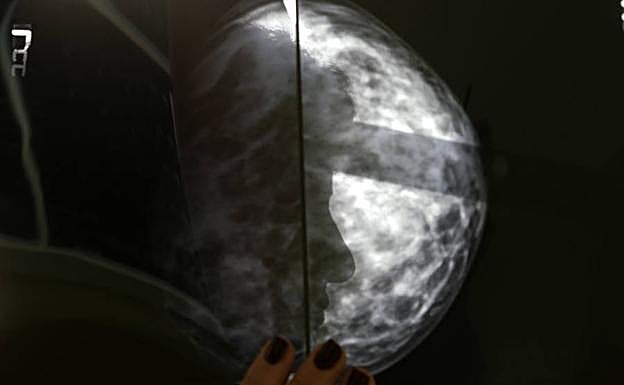

Mamografía. Reuters

La inteligencia artificial se adelanta al cáncer de mama

El MIT es capaz de predecir a partir de una mamografía si la paciente es propensa a desarrollar un cáncer de mama en el futuro

Investigadores del Hospital General de Massachusetts y el CSAIL trabajan en el desarrollo de un algoritmo capaz de predecir a partir de una mamografía si la paciente es propensa a desarrollar un cáncer de mama en el futuro.

Para ello, el equipo de investigación han revisado un total de 90.000 mamografías de detección de alta resolución de aproximadamente 40.000 mujeres para entrenar, validar y probar el modelo de aprendizaje profundo. «Hay mucha más información en una mamografía que solo las cuatro categorías de densidad mamaria», señala Adam Yala, autor principal del estudio.

La densidad mamaria es un factor de riesgo independiente para el cáncer de mama que se ha agregado a algunos modelos para mejorar la evaluación de riesgos. El entrenamiento ha permitido a esta inteligencia artificial reconocer los sutiles patrones del tejido mamario que son precursores de su malignización.